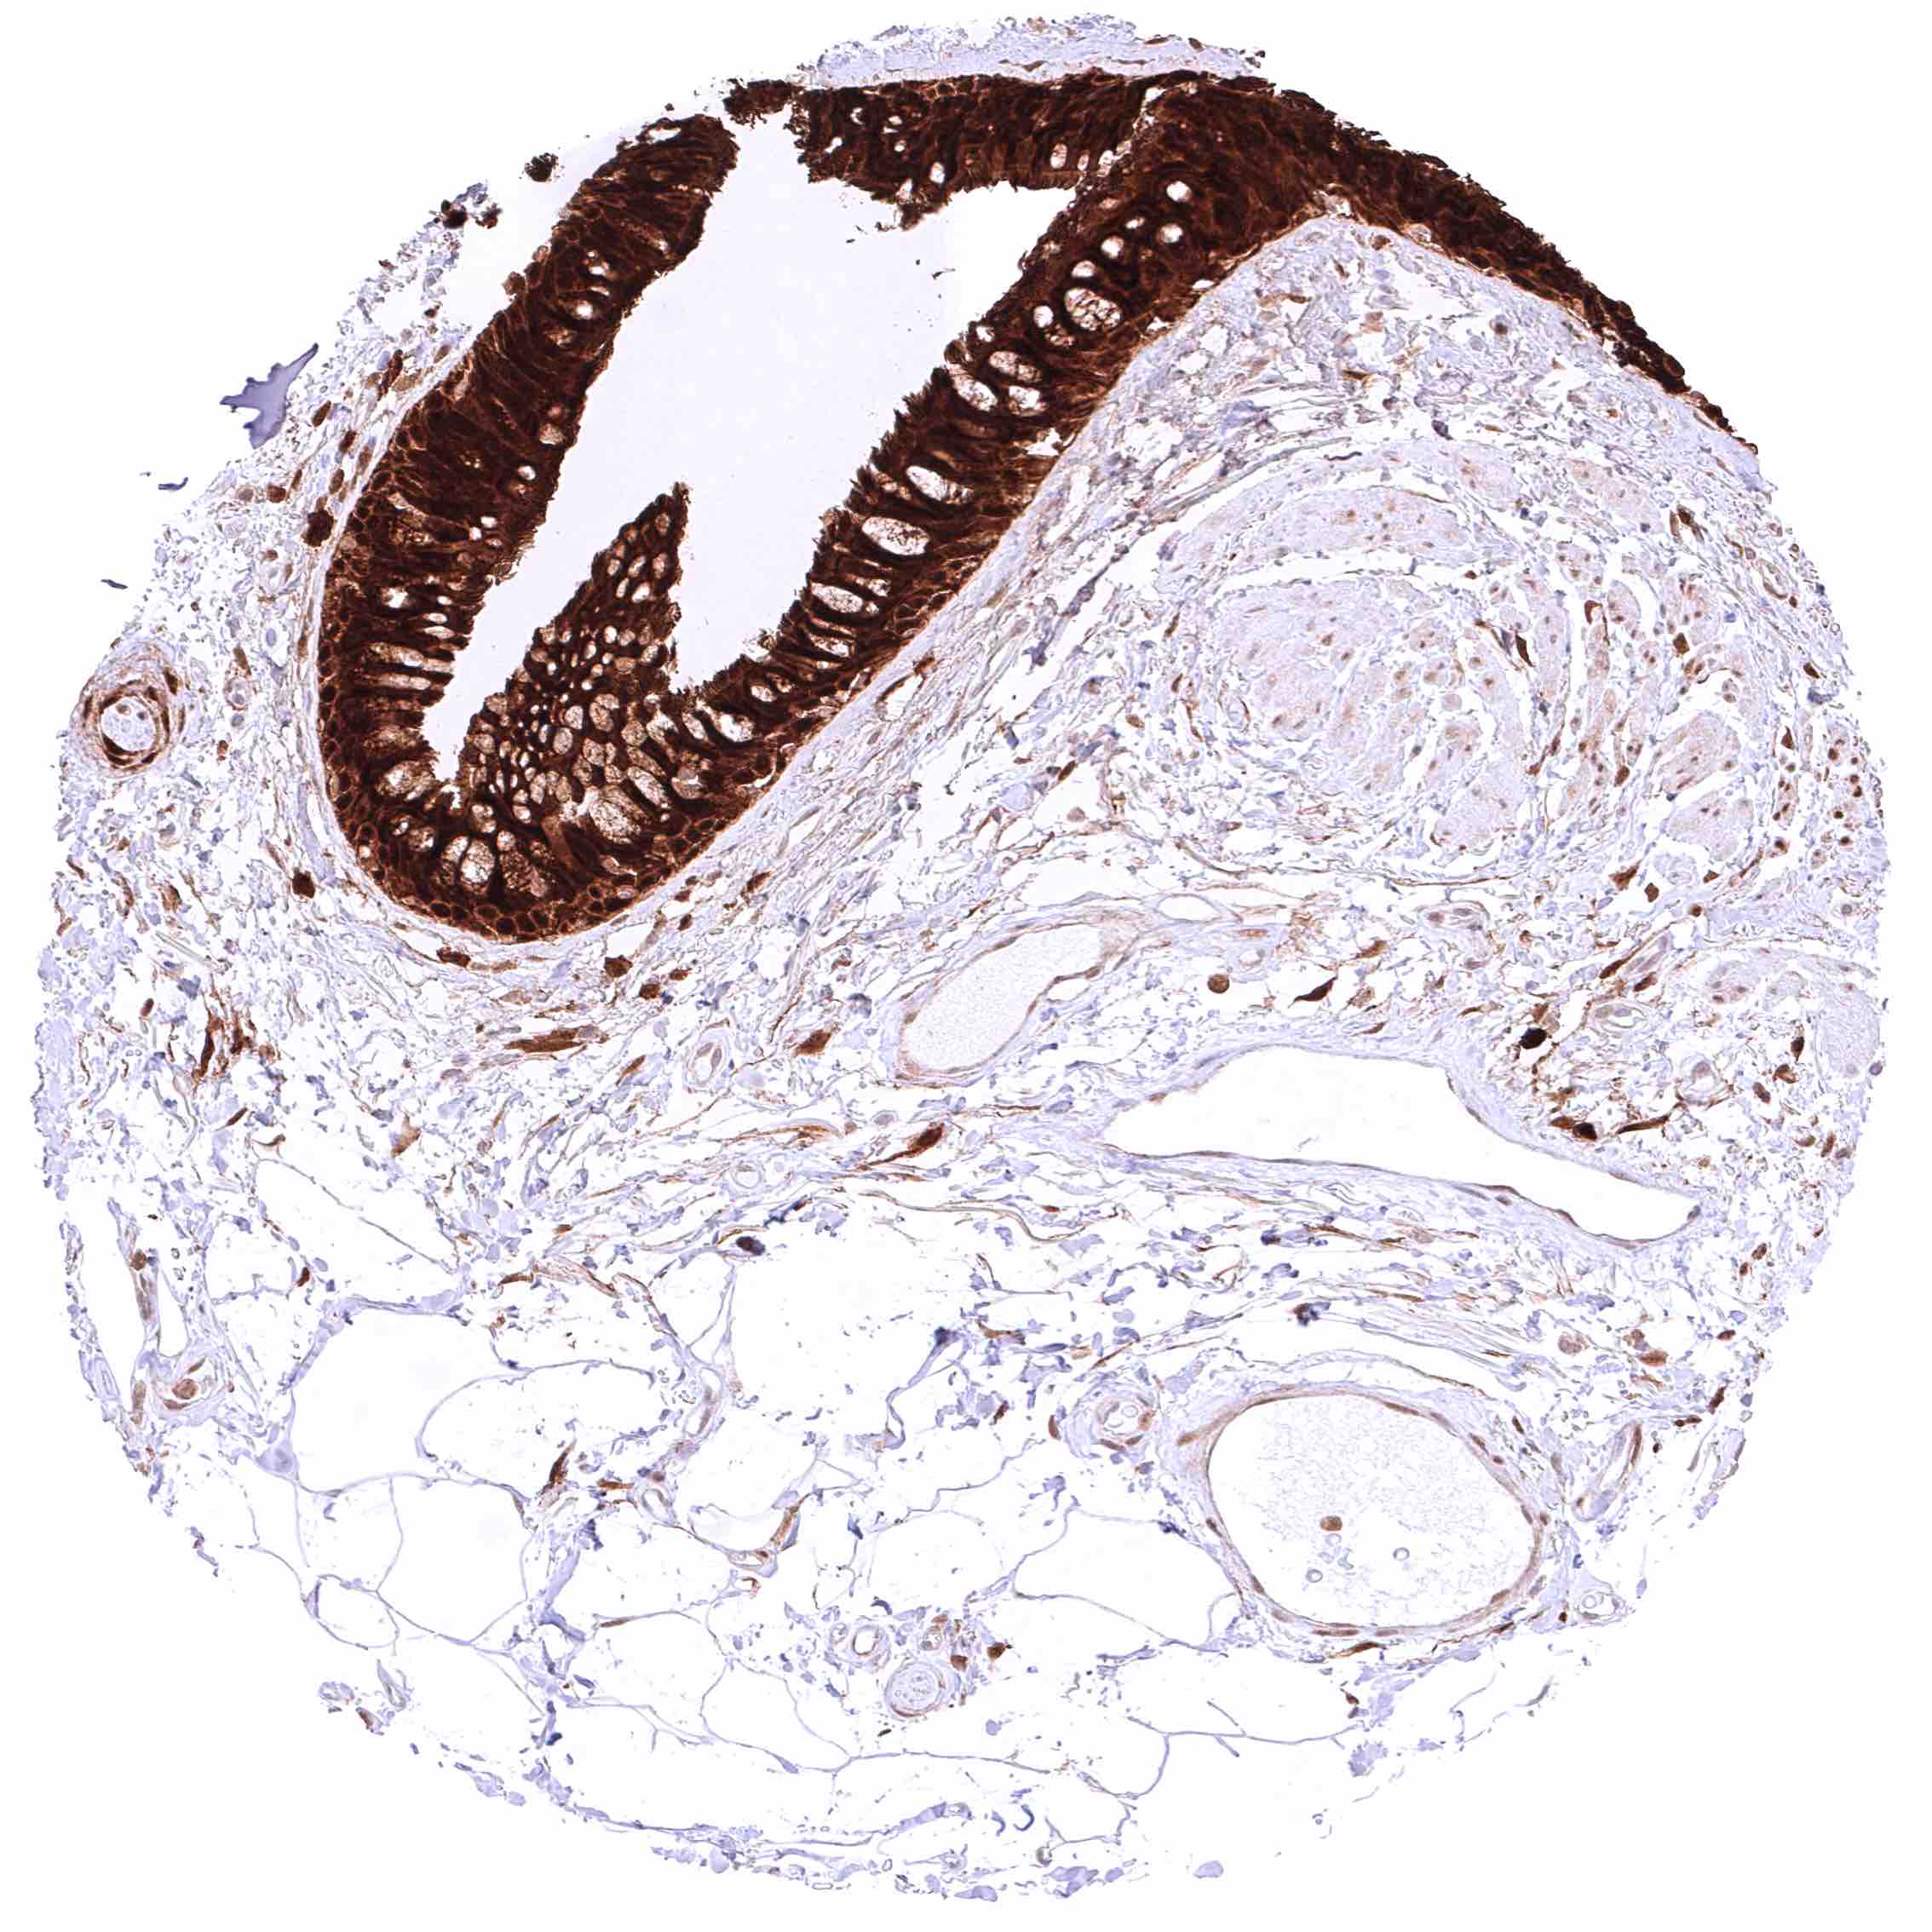

Appendix, mucosa – Strong, predominantly cytoplasmic GSTP1 positivity of epithelial cells. Staining is most intense at the base of crypts and decreases slightly towards the surface epithelium.